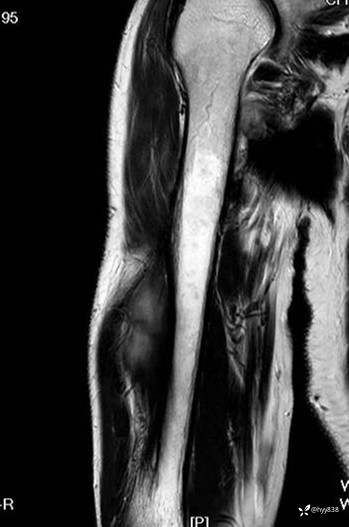

SAG T1WI+PDWI fs

COR T2WI